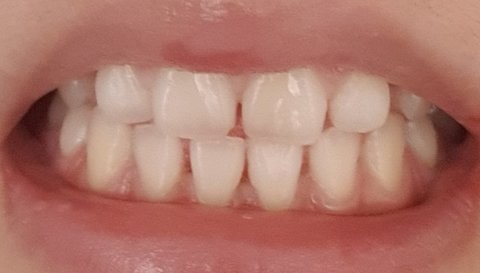

벌어져있긴했지만 보기싫을 정도는 아닌 것 같아서요

저 정말 해야 될 정도인가요??

그정도 라면 전 안해요 전 돌아간다면 안해요 ㅋㅋㅋ 부정교합도 아니고 치열이 이상해 보이지도 않아요 그냥 조금 벌어진.정도라면 안해도 될거같아요 나열하신 부작용이 눈에.보이진.않아서 모르겠으나 확실히 약해진건 맞아요~억지로 당기고 조이는데 약해지것죠~

엥? 저렇게 벌어져 있을 정도면 해야되는거 아닌가.. 나도 지금 교정 중이고 저정도면 해야될 거 같은데.. 치아 쪼일 땐 아프지만 친구들한테 교정하고 점점 예뻐진다는 소리 들을 때마다 괜히 했다 싶진 않음